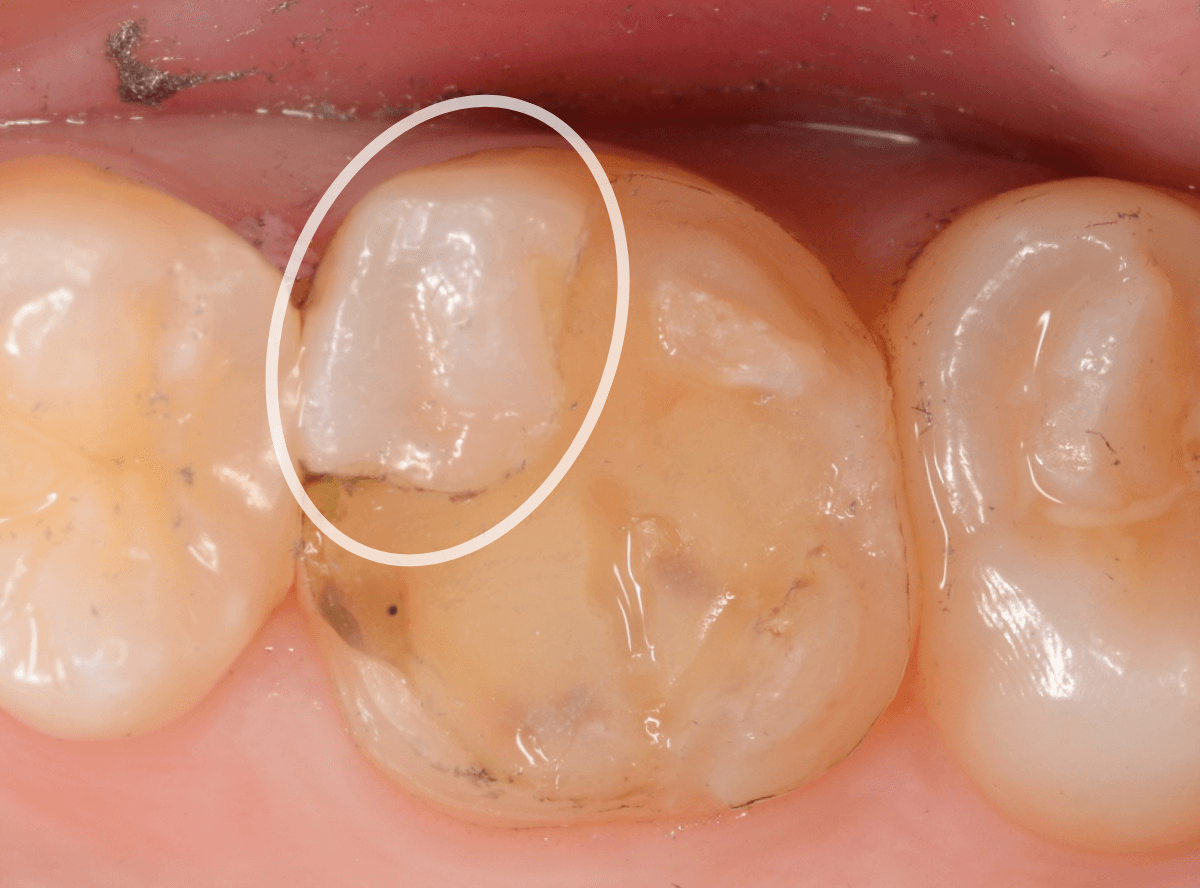

歯を裏側から見たところです。

幸い、見える部分に虫歯が

さし歯と歯肉の間に虫歯ができているのがわかります。

歯の奥まで虫歯が進んでいるのか、浅い虫歯ですんでいるのかは治療をしながら調べていく必要があります。